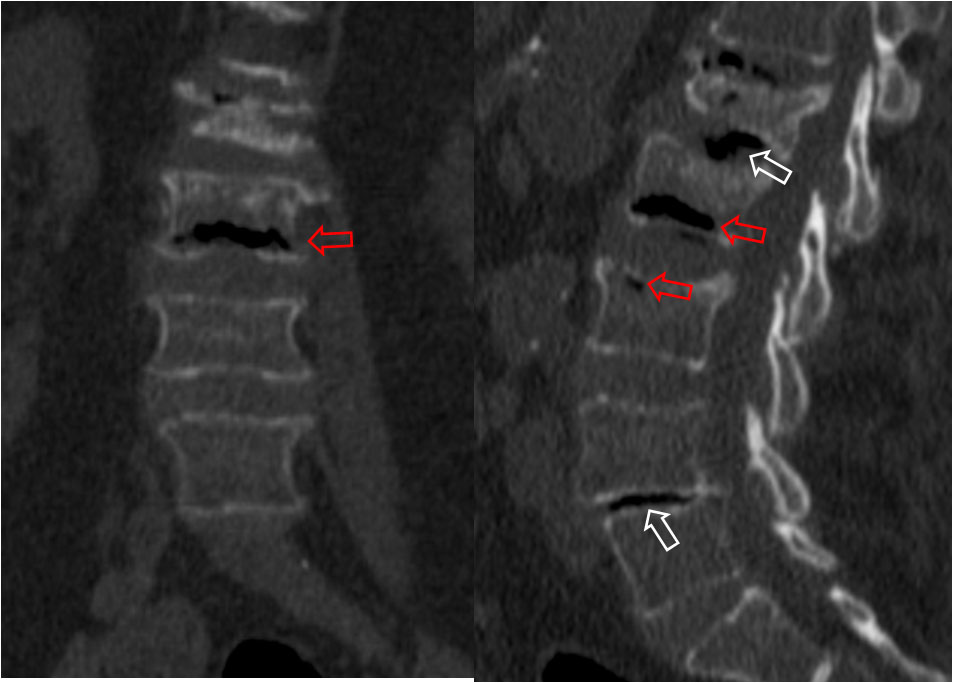

SIGNO DE LA C

Signo de coalición subtalar (fusión calcáneo-astragalina) en la radiografía lateral del tobillo. La «C» se forma por el límite medial de la cúpula talar y el límite posteroinferior del sustentaculum tali.

En la radiografía lateral de tobillo hemos marcado con flechas la «C» que da nombre al signo.

La fusión calcáneo-astragalina (flecha) se comprueba en el corte coronal de TC de tobillo.

Referencia: Lateur LM y cols. Subtalar coalition: diagnosis with the C sign on lateral radiographs of the ankle. Radiology 1994; 193: 847-851.